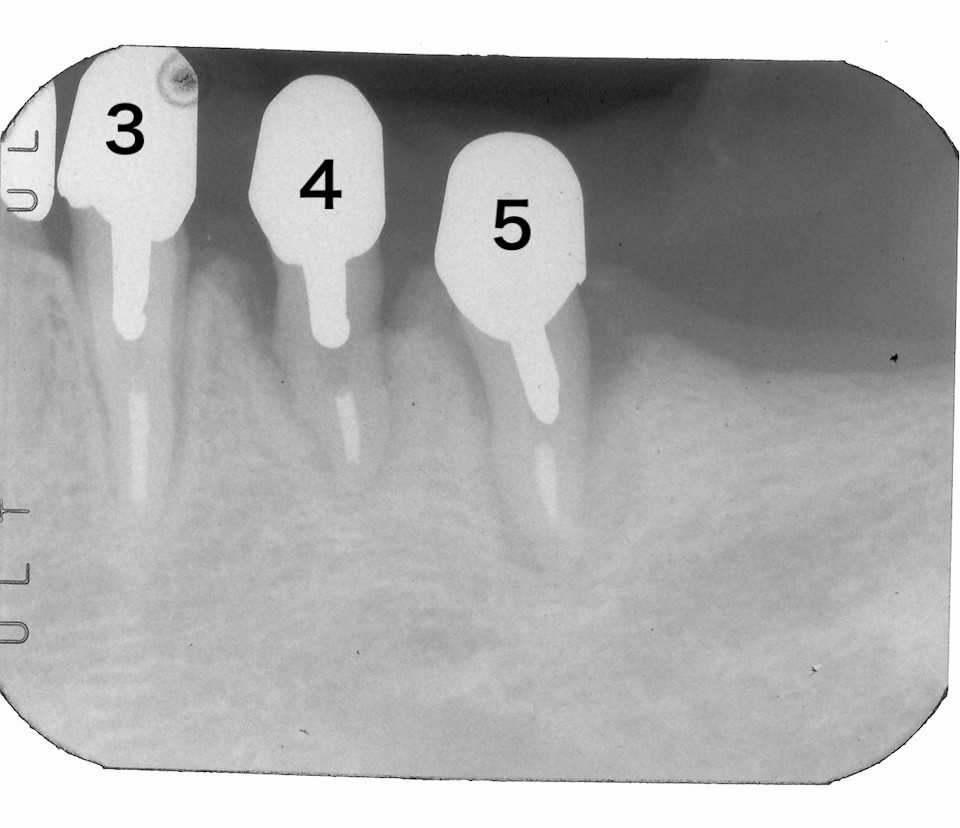

40代女性、右上345、外傷性カリエス、自発痛+ちょっと目を離すと虫歯になり、痛いです。。とやってくる。歯ぎしり食いしばりがあるので、ナイトガードを作ってはいるのだが、鬱陶しいとかでサボっている。標準治療では痛みがあれば神経を取って冠を被せることになるのだが、本人はそんなことは知らない。うちに来れば1回で治るので大したことはないと気にしていない。今日は痛みの出ている右上5を主に処置する。僕が使っているボンディング材はこちら。α-TCPに3MIXを耳かき一杯添加し、50%クエン酸で練る。この上からCRダイレクトボンディングでカバーする。3MIXの作り方はこちら。α-TCPの入手法はこちらでは時系列でどうぞα-TCPの製造元を公開した所為か、α-TCPの入手性が良くなっているように感じる。少しずつここの治療法が広まってくれると嬉しいのだが。ここからは実際のCRでの再建なのだが、使用する材料や器具もなんでも良いというわけではないと思う。ここのFreepage list を参照して欲しい。ここで使っている材料器具は全て公開している。ストリップス(隔壁)を使わずに隣接面窩洞のCR充填(というよりは修復)ができるというのは常識外の話で、一般の歯科医師はやってみたことも考えたこともないとは思う。そもそも歯学部では習わないからだと思う。しかしできないことはなく、辺縁漏洩も気泡が入ることもないので長期的に予後は良好となる。